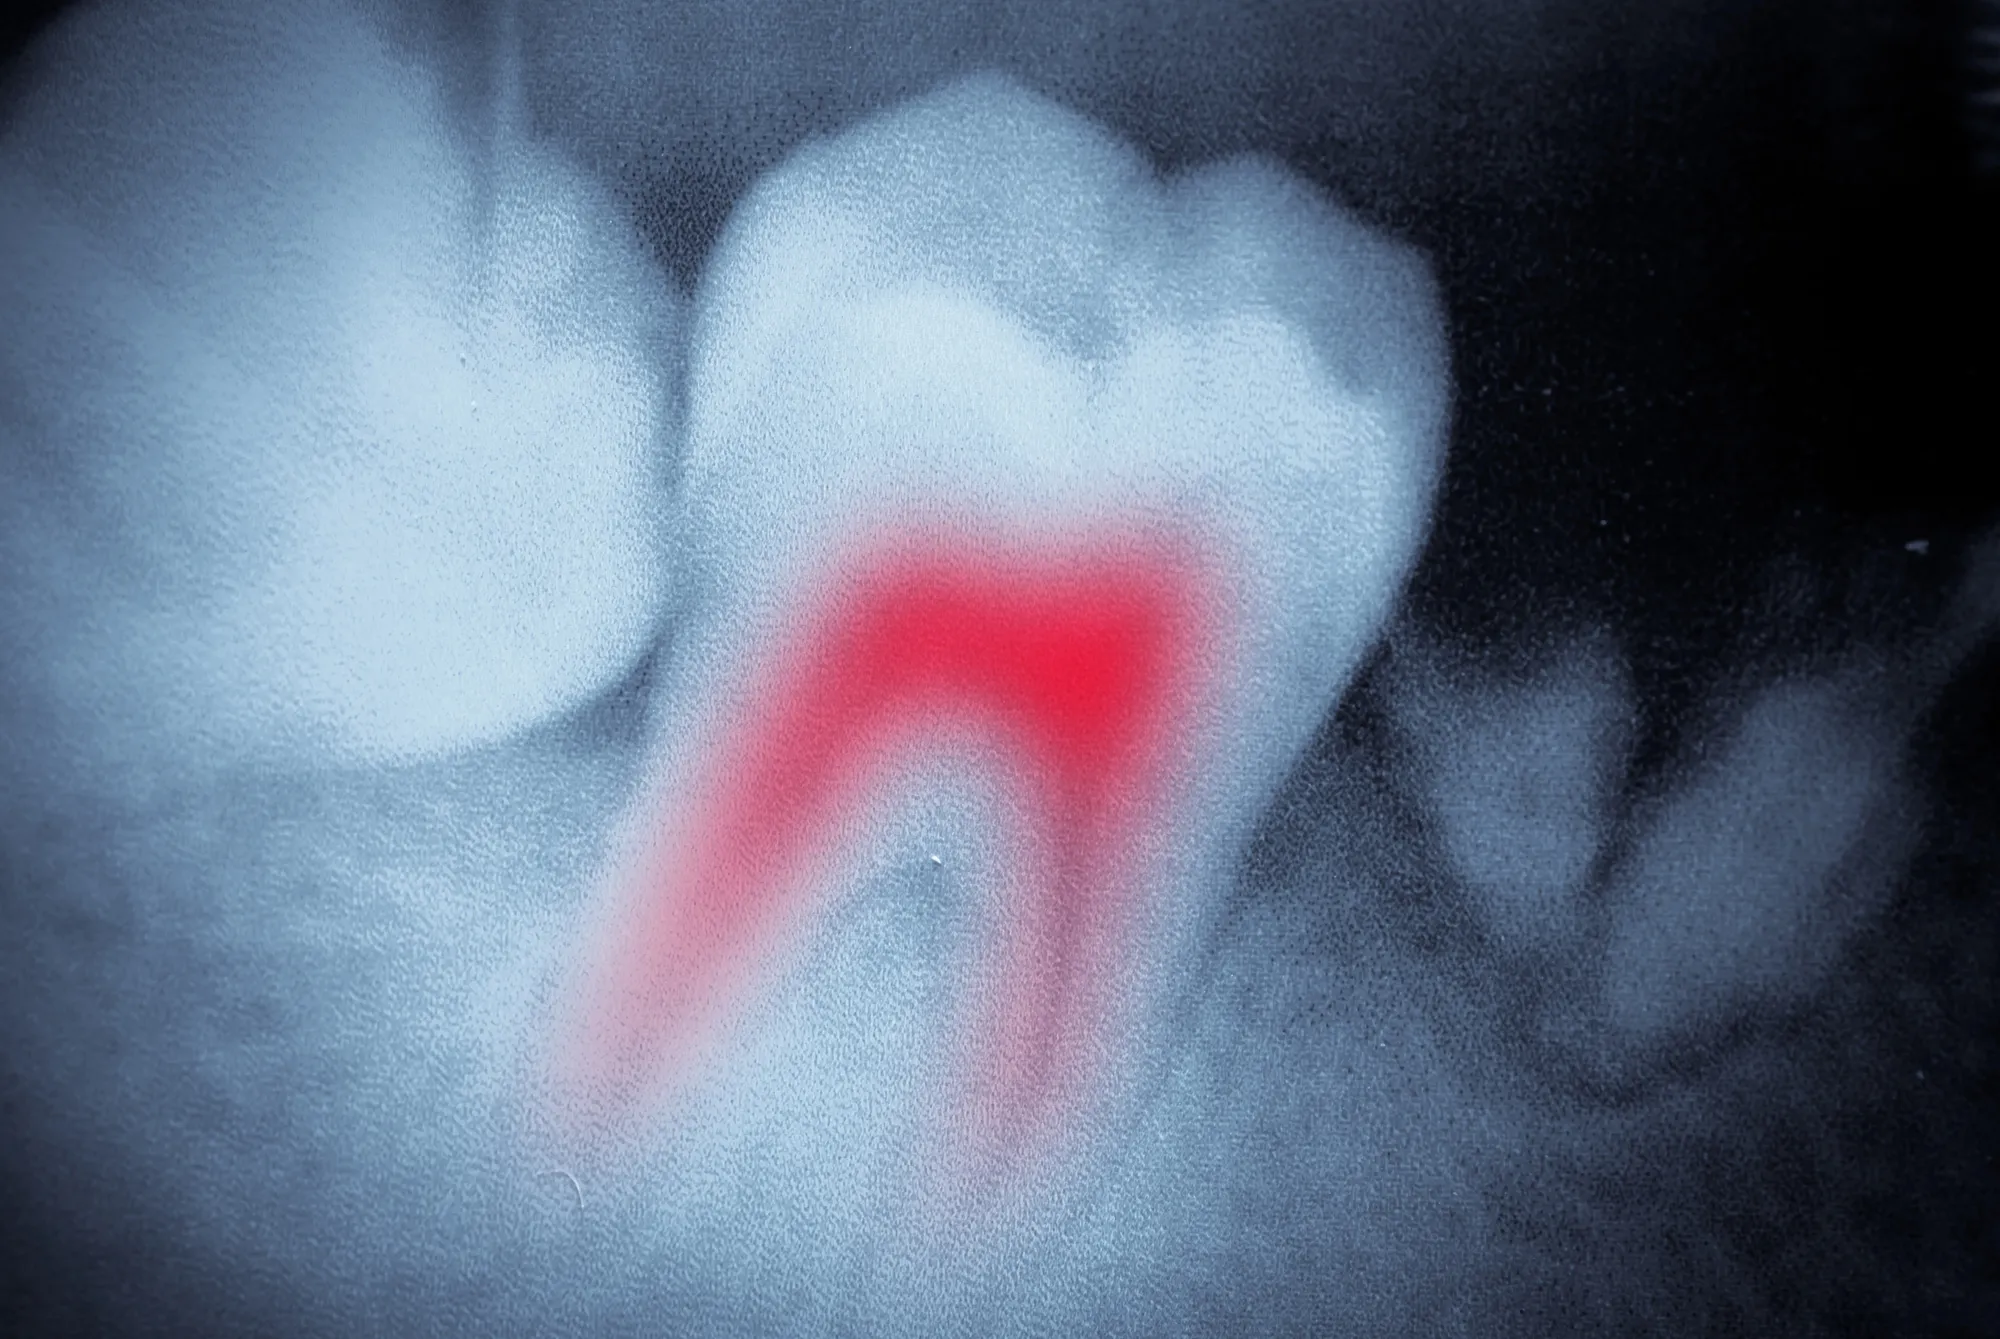

When Is a Root Canal Necessary?

We recommend root canal therapy when the pulp becomes infected or inflamed due to:

- Deep cavities or decay

- A cracked or chipped tooth

- Repeated dental procedures on the same tooth

- Trauma that damages the inner tooth structure

You may notice signs such as prolonged sensitivity to hot or cold, swelling near the tooth, or ongoing pain. If any of these sound familiar, a root canal could be the right step to protect your smile and bring lasting relief.